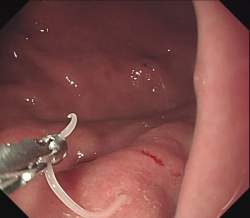

15無念Nameとしあき25/11/28(金)01:10:15No.1369234506+

>一度胃に入ったらどうやって駆除するの?

スレ画

16無念Nameとしあき25/11/28(金)01:10:45No.1369234578そうだねx2

手術で摘出か胃酸で溶けるの待つ

17無念Nameとしあき25/11/28(金)01:10:45No.1369234579そうだねx2

胃カメラでつかみ取る